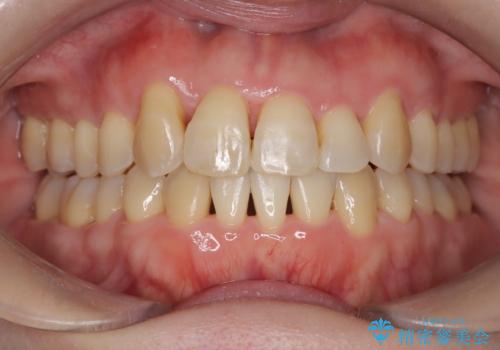

【インビザライン】ずれた前歯の噛み合わせをなおしたい

- 前歯の噛み合わせが悪いことを主訴に来院されました。

歯周病も併発していたため、歯牙への負担が少なくなるように治療計画をたて、インビザラインにて治療を完了しました。

矯正開始前に半年間、歯周治療を行ってからインビザラインを装着しています。